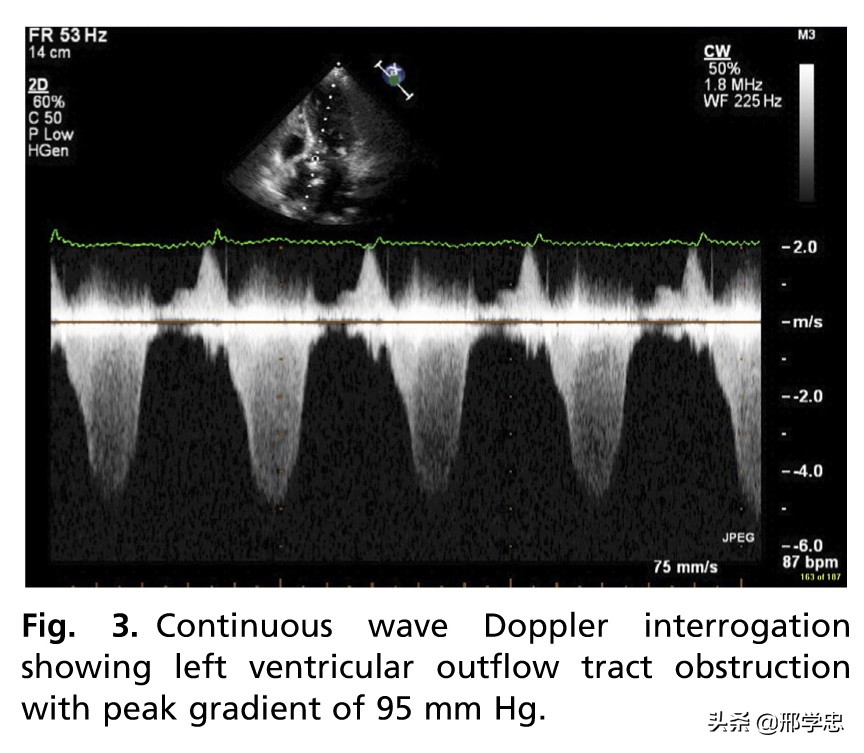

左室流出道梗阻在SIC中占10%-25%。经常合并二尖瓣反流,常见于心尖膨大样SIC(图3)。

经胸心动超声是评估可疑SIC患者的一线无创治疗。经胸心动超声联合多普勒超声可以快速评价急性期的左室功能异常(图1),还可以发现潜在的并发症无左室流出道梗阻(图3)和室性血栓(图4)等。这些信息对于患者的成功处理、风险评价和康复的监测是十分关键的。